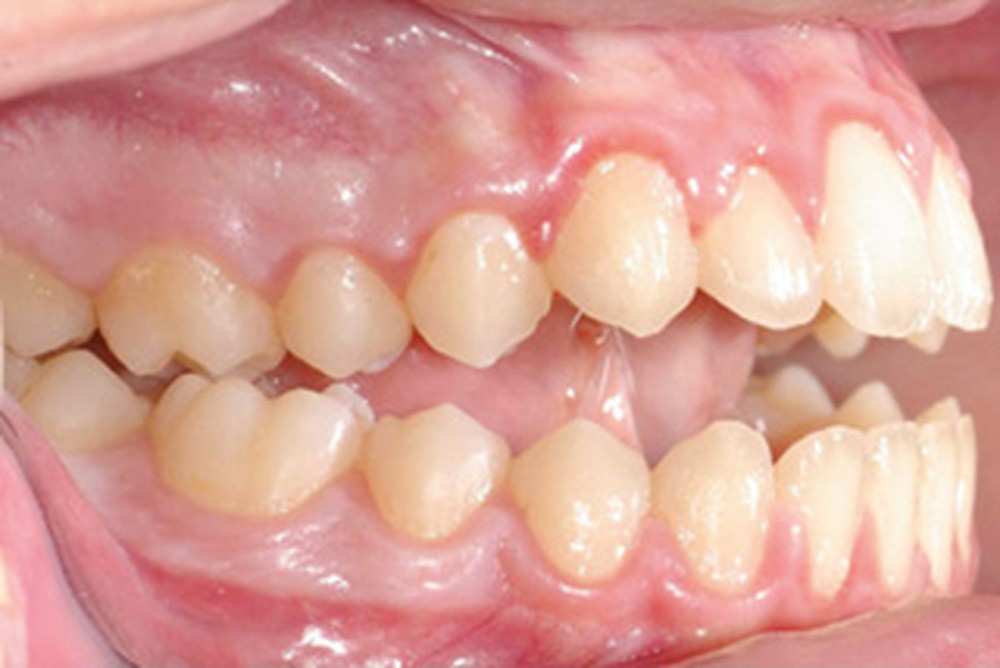

Quelques années plus tard, au moment de démarrer sa prise en charge orthodontique, la patiente présentait à nouveau une béance antérieure, un décalage des milieux incisifs de 2 mm et le problème transversal avait récidivé. Lors de l’examen clinique, elle présentait un inversé d’occlusion bilatéral postérieur et une ventilation buccale exclusive. À la suite du refus de réaliser l’amygdalectomie de façon précoce, elle ronflait toujours et sa déglutition ne s’était pas modifiée malgré des séances d’orthophonie (fig. 7 à 15).